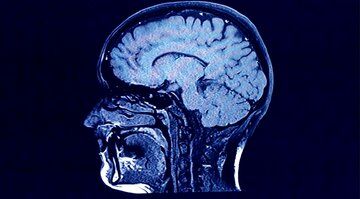

در سال ۲۰۱۳، اسپالدینگ و همکارانش، با بهرهگیری از سنبله بمب، به بررسی گردش سلولهای مغزی پرداختند. سالها محققان بر این باور بودند که تعداد نورونهای مغز در سنین کودکی، ثابت و مشخص است و بررسیهای پیشین خانم اسپالدینگ نشان داده بود که این ماجرا درباره مناطقی مثل قشر مغز صادق است. اما او و تیمش با استفاده از کربن ۱۴ و تاریخگذاری نورونهای هیپوکامپ تائید کردند که در طول دوران بزرگسالی هم امکان تولید نورونهای جدید وجود دارد.